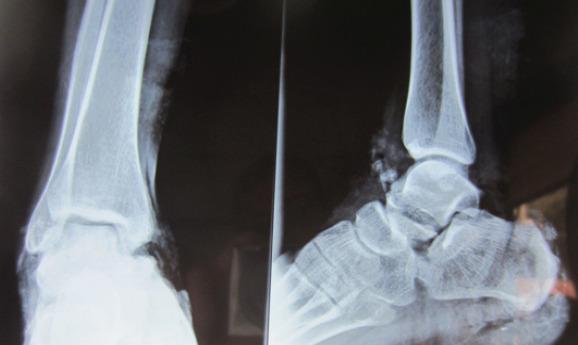

A 23-year-old male who sustained a high-energy trauma due to road traffic accident. He presented to ER with fracture of shaft femur, multi-ligament injury at the ipsilateral knee, fracture lower pole patella, ipsilateral fracture talus, and calcaneus along with comminuted fracture femoral head. He was managed by open reduction and internal fixation of the femoral head by safe surgical dislocation of the hip joint. Such injuries have been described rarely in the literature until now. The purpose of this report is to highlight the extreme rarity, possible mechanism involved, surgical management, and functional outcomes of such injuries.